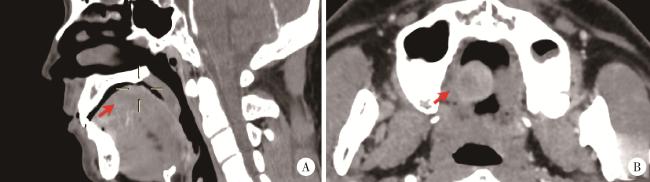

2.2 典型病例2

女性,60岁,因“发现右舌腹溃疡3月”就诊。患者就诊3个月前发现右舌腹黏膜溃疡,初为鱼眼大小,逐渐增大,伴轻度疼痛,未行诊治。追问病史,患者近期精神压力较大,否认食物和药物过敏史,既往史无特殊。专科检查(图 5)发现右舌腹黏膜火山口状溃疡,直径约1.5 cm,表面未见假膜,边界不清(图 5A)。触诊病变质韧,周围组织有硬性浸润,触痛。白细胞计数9.36×109 /L,中性粒细胞比例80.2%;中性粒细胞绝对值7.5×109 /L;嗜酸粒细胞比例0.3%,嗜酸粒细胞绝对值0.03×109 /L。初步诊断为右舌肿物(鳞状细胞癌?)。

图5 病例2,右舌侧缘溃疡

Figure 5 Case 2, an ulcer on the lateral margin of the right tongue

A, appearance of ulcer at the initial diagnosis; B, one week after biopsy, the lesion is smaller than before; C, one month later, the ulcer in the anterior part of the right lingual margin disappeared, and an ulcer appeared in the posterior part of the right lingual margin with rough surface; D, one year later, a mung bean-sized ulcer appeared(arrowhead).

因患者初诊印象疑为鳞状细胞癌,拟切取活检后收入院行手术切除。活检病理报告为黏膜溃疡,表面大片坏死及纤维素渗出,基底血管内皮细胞增生、肥大,呈泡状核,偶见核分裂象。慢性炎症细胞浸润,累及深层肌组织,较多嗜酸粒细胞浸润,倾向于嗜酸性溃疡(图 6)。患者未行治疗。活检后1周,右舌侧缘前部溃疡较前缩小(图 5B),1月后复查,右舌侧缘前部溃疡消失,但在其后部出现溃疡,表面不光滑,无触压疼痛(图 5C)。嘱患者继续观察。1年后复查,右舌侧缘黏膜未见溃疡,仅见少许瘢痕,舌腹黏膜见一个约绿豆大小溃疡(图 5D)。